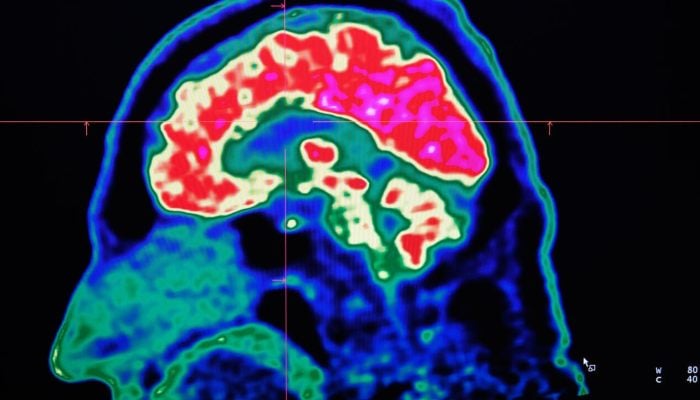

PARIS: Tiny shards of plastic called microplastics have been detected accumulating in human brains, but there is not yet enough evidence to say whether this is doing us harm, experts have said.

These mostly invisible pieces of plastic have been found everywhere from the top of mountains to the bottom of oceans, in the air we breathe and the food we eat. They have also been discovered riddled throughout human bodies, inside lungs, hearts, placentas and even crossing the blood-brain barrier.

The most prominent study looking at microplastics in brains was published in the journal Nature Medicine in February.

The scientists tested brain tissue from 28 people who died in 2016 and 24 who died last year in the US state of New Mexico, finding that the amount of microplastics in the samples increased over time.

There have also been experiments carried out on mice, including a study in Science Advances in January which detected microplastics in their brains.

The Chinese researchers said that microplastics can cause rare blood clots in the brains of mice by obstructing cells — while emphasising that the small mammals are very different to humans.